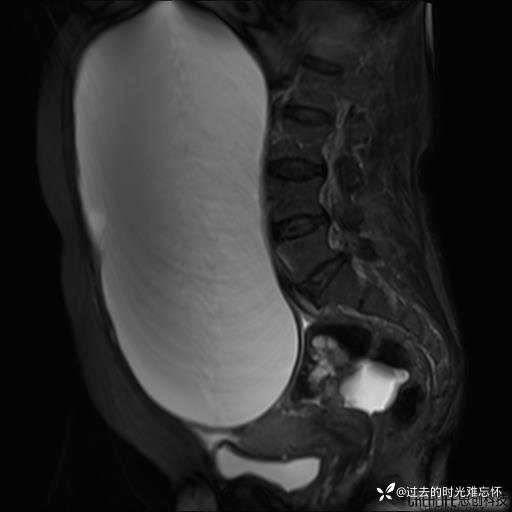

患者性别:女

患者年龄:65岁

主诉: 发现腹部隆起半年余。无其他明显不适。

浆液性囊腺瘤 (22)